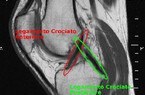

PERIOSTITE: cosè?

Vucinic non ci sarà col Chievo: periostite al ginocchio destro